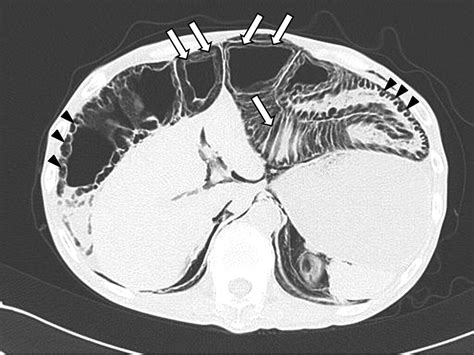

CT Scan The gold standard; provides detailed visualization of gas cysts.

When reviewing imaging, radiologists look for the specific appearance of "bubbly" gas collections along the serosal or submucosal surfaces. Differentiating these cysts from free air (pneumoperitoneum) is the most critical step for the radiologist to ensure the patient is not facing a surgical emergency.